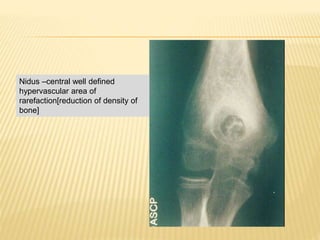

RADIOLOGICAL FEATURES

 A sharp round or oval lesion.

 Less than 2 cm in diameter.

 Radiolucent nidus surrounded by reactive sclerosis

 Nidus- osteolytic/partially/entirely calcified

Nidus –central well defined

hypervascular area of

rarefaction[reduction of density of

bone]